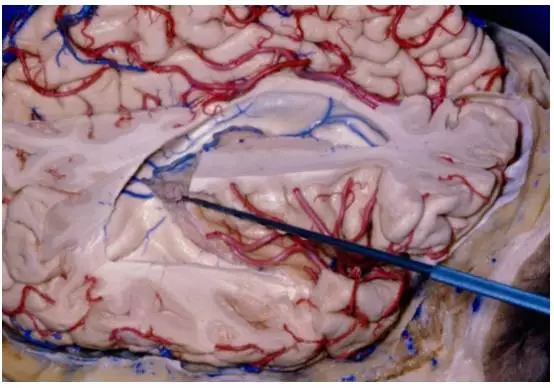

图5. 经纵裂到达侧脑室房部的冠状位解剖图。已去除部分右侧顶上小叶(插图来自AL Rhoton,Jr)。